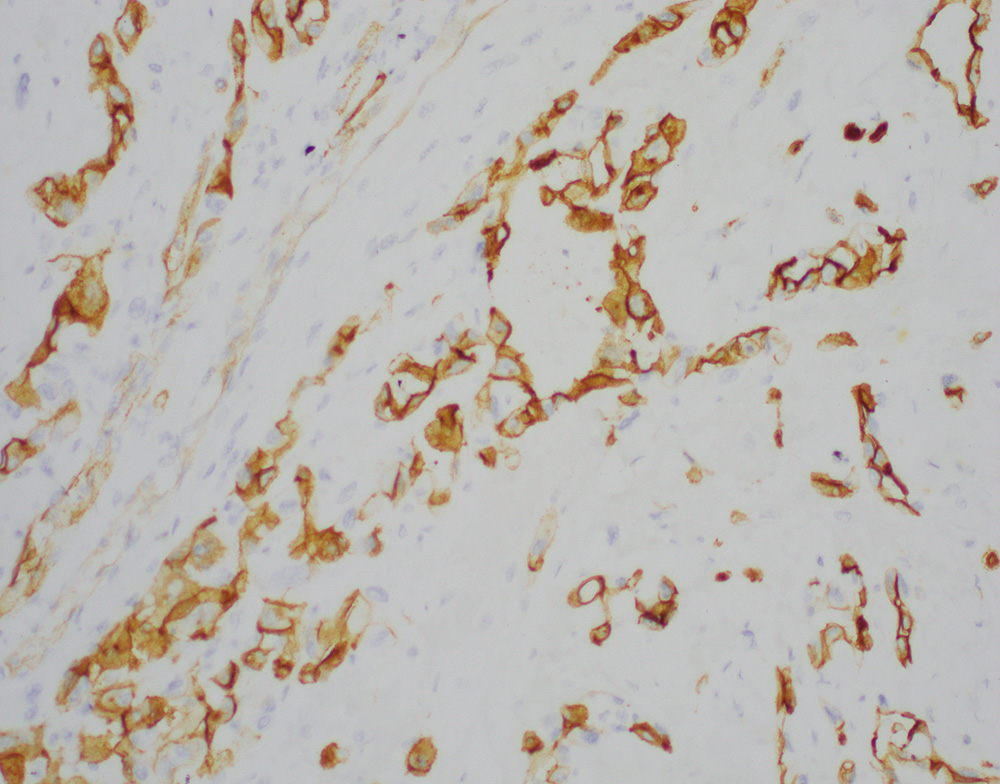

A bone biopsy showed a poorly differentiated epithelioid neoplasm with pleomorphic nuclei, prominent nucleoli (Figures-1, 2) with foci of necrosis. The tumor cells were positive for keratin 7 (Figure-3) with patchy positivity for pan-keratin, while they were negative for PAX8, SOX10, keratin 20, TTF-1, p40, NKX3.1, CDX2, and GATA3. Given the keratin positivity, the tumor was felt to represent metastatic carcinoma. The patient also had several skin nodules involving the posterior leg. A skin biopsy demonstrated numerous irregularly shaped anastomosing and infiltrative vascular channels lined by atypical endothelial cells (Figure-4). The neoplastic cells were positive for ERG, CD31 and CD34 (Figure 5). Re-evaluating and staining the bone biopsy with vascular markers showed positive ERG staining in the neoplastic cells.